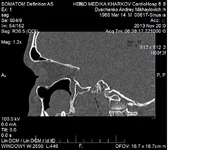

Вот и ко мне пришла очередь на операцию! Наделал снимков кучу и КТ И 3Д.

Одна киста в правой гайморовой пазухе, а вторая в челесте с левой стороны но вроде в пазуху не вышла. Буду делать в Областной.

Вкладення

• .webp

.webp

61.7 КБ · Перегляди: 1212